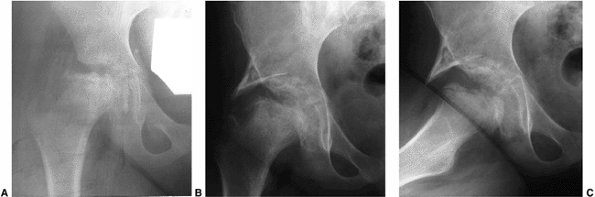

Figure 25.26

A 9-year-old boy presenting with hip pain, nonresponsive to nonsurgical measures. Clinical abduction is to 10 degrees; adduction is to 40 degrees with the hip in extension. A: Antero-posterior view of pelvis showing total femoral head involvement in reossification stage of disease. B: Lauenstein view. C: Arthrogram in neutral position showing considerable flattening of femoral head and slight impingement on lateral edge of the acetabulum. D: Arthrogram in abduction demonstrating hinge abduction. E: Arthrogram in adduction demonstrating reasonable congruity between femoral head and acetabulum; note normal contour of lateral acetabular edge. F: Abduction osteotomy allowing 45 degrees of abduction and 0 degrees of adduction. G: Three years postoperatively. Patient is pain-free with 45 degrees of abduction, 10 degrees of adduction, and good rotation. H: Lauenstein view 3 years postoperatively. |